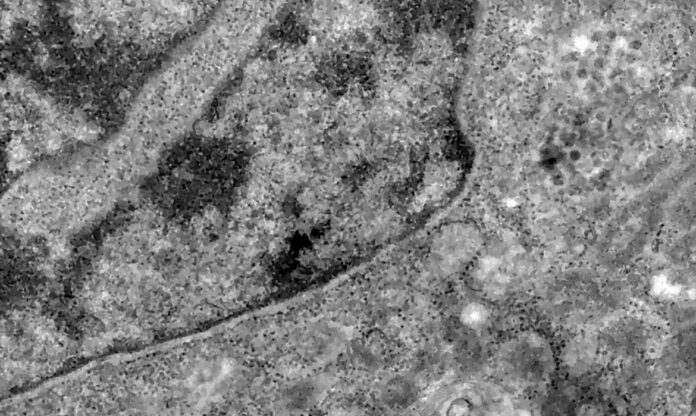

Pesquisadores brasileiros conseguiram, pela primeira vez, detectar a presença do coronavírus em retinas. O estudo pode contribuir para compreender melhor a dinâmica do vírus e as sequelas em pacientes infectados.

Os pesquisadores analisaram retinas de pacientes que morreram em decorrência da covid-19 e compararam com fotos dos olhos desses pacientes quando vivos para analisar as diferenças e formas de aferir a presença do vírus a partir da retina.